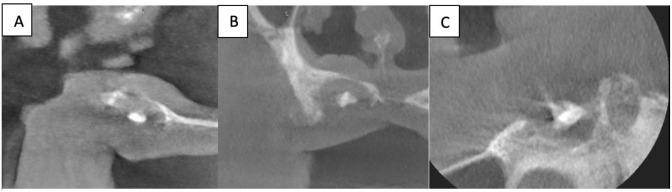

Fungus Ball (FB) is a non-invasive fungal infection caused mainly by species. It can occur after root canal treatments are applied to the teeth adjacent to the maxillary sinus. These balls are commonly seen in the paranasal sinuses and rarely observed in the nasal cavity. This report attempted in to highlight such a rare case of fungal infection which requires accurate observation. Moreover, it highlights the importance of careful microbiological and histopathological examinations that were combined with imaging and can lead to a definitive diagnosis.

Herein, we report a rare case of a FB found in the vicinity of the nasal cavity of a 73-year-old male patient. Microbiological examination supported by radiographic and histopathological results indicated that the FB is due to . Excised surgery was done to the FB area, and the patient was referred to the post-operation room with the proper recommendations. After the wound healed, the total denture was performed as requested by the patient, and his overall oral health was improved.